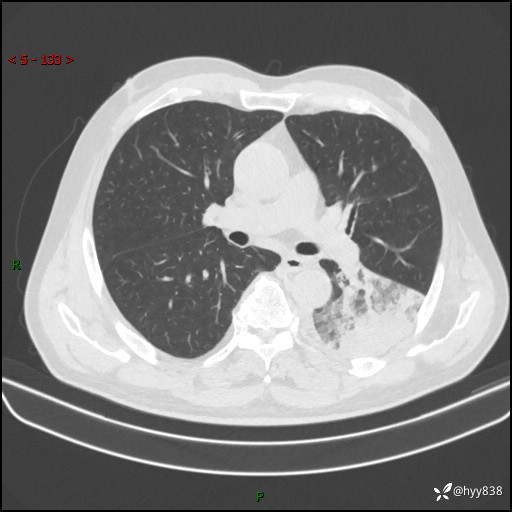

59岁/男,发热伴咳嗽3天。白班偶遇,“大叶性肺炎”,病原体挑战---结果公布~

【患者信息】:59岁/男

【主诉】:发热伴咳嗽3天

【现病史及既往史】:患者3天前无明显诱因出现发热,体温最高达38.6℃,伴有咳嗽,干咳为主,感乏力、肌肉酸痛,无明显头晕头痛、鼻塞、流涕、呼吸困难、胸痛、恶心呕吐、腹痛腹泻、尿频尿急等不适,于当地诊所输液治疗3天感症状无好转,仍有间断发热、咳嗽,现为求进一步诊治,于我院门诊就诊,门诊以“发热待查”收入我科进一步诊治。 患者自发病以来,精神、饮食、睡眠欠佳,大小便正常,体力、体重无明显变化。

【检查】:胸部CT平扫